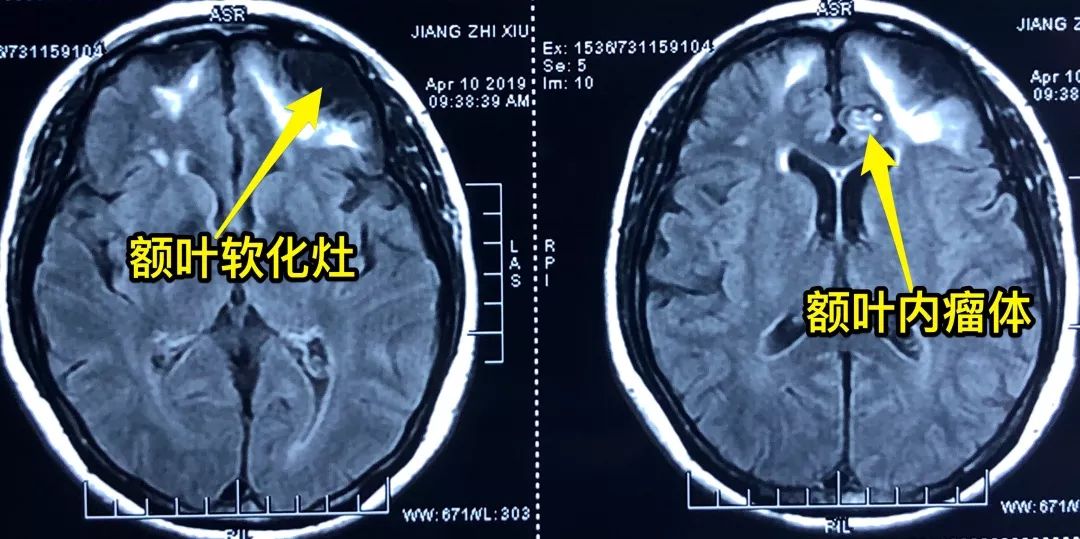

头颅MRI增强显示:左侧额叶中线旁爆米花样混杂信号肿块,双侧额叶、颞叶软化灶伴胶质增生。脑电图显示:左额有癫痫样放电。

结合CT、MRI增强、脑电图检查结果,诊断为:左侧额叶海绵状血管瘤,左额叶软化灶,患者之前的头晕、头痛症状就是因此引起。患者目前不仅有海绵状血管瘤,并且脑电波异常,虽然目前没有明显的癫痫样发作,但是以后严重了会出现临床症状,刘长青教授建议患者手术治疗,切除海绵状血管瘤,解除出血风险,同时去掉癫痫灶。